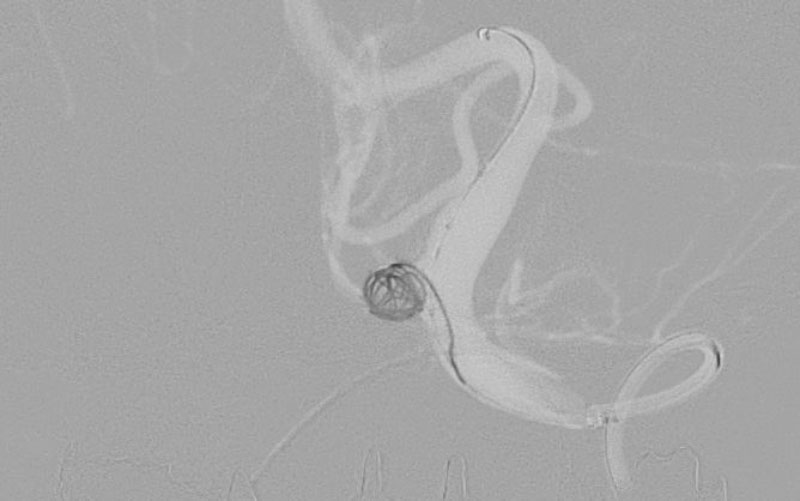

'26年4月

左後下小脳動脈瘤

80代

大阪府の病院

No.1631 手術前

No.1631 手術中

No.1631 手術後